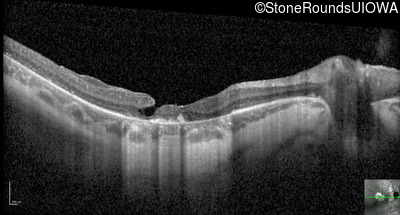

Optical Coherence Tomography - Right - 10/100 -1

Exemplar / OCT Stack